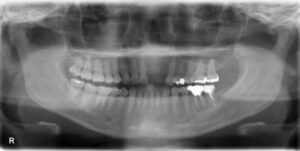

インプラント治療を成功させるうえで重要なのは、精密な治療計画です。そのためには顎の骨の状態を精密に把握する必要があります。そこで活躍するのが歯科用CTです。これまでのレントゲン検査とはくらべものにならないほどの詳細な情報を立体画像で確認することができます。

顎の骨の骨密度や厚み、さらに神経や血管の位置まで把握できるので、どの位置にどの角度でどれくらいの深さにどの種類のインプラントを埋入すればいいのかの綿密なシミュレーションが可能です。